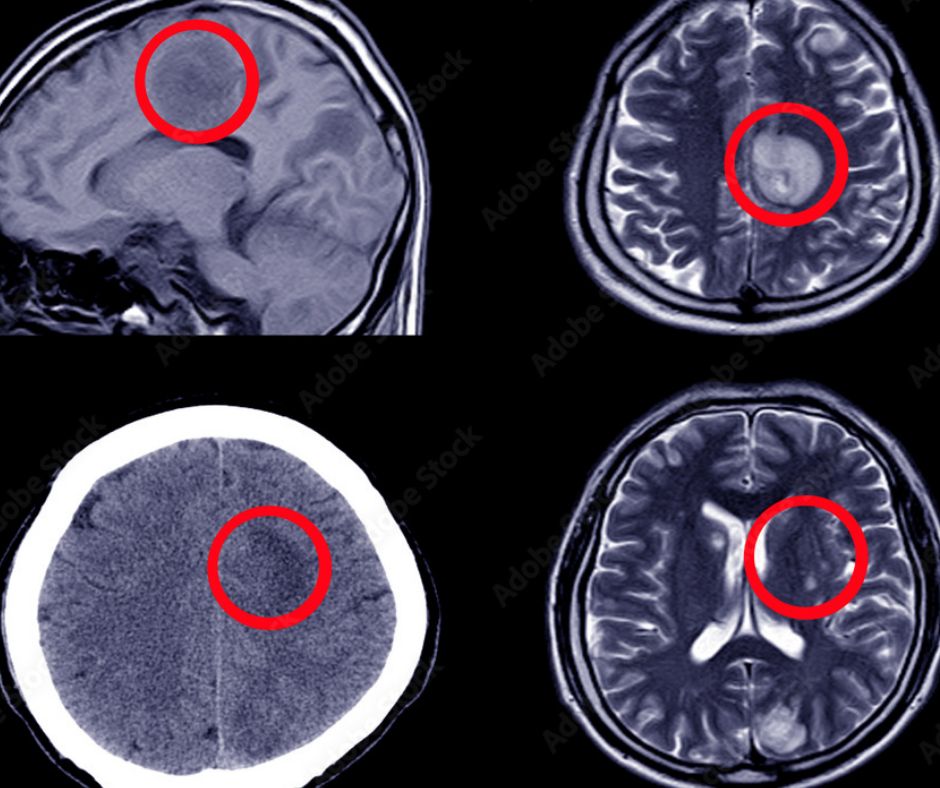

Researchers say the complementary use of artificial intelligence may significantly improve the accuracy of radiologists in diagnosing intracranial aneurysms.